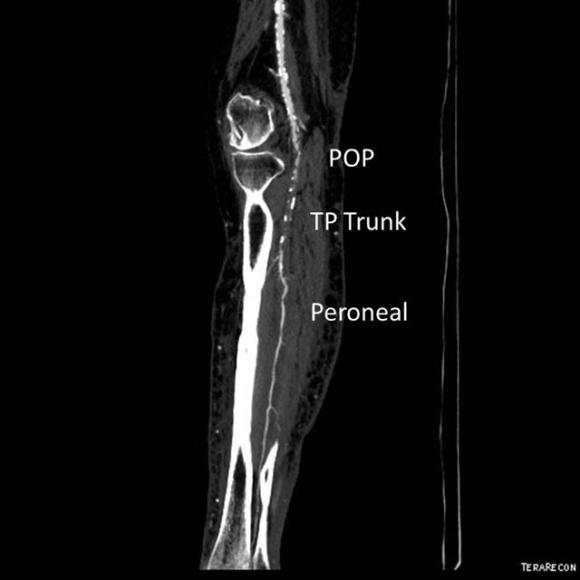

The patient is a gentleman from out of state who had called about problems he was having with walking and with leg ulcers that wouldn’t heal. He is in his seventies and has a pacemaker for an arrhythmia for which he was on Xarelto. He also had type II diabetes. He had bilateral lower extremity deep venous thromboses 6 years prior requiring IVC filter placement. The filter occluded, and it resulted in sudden sharp and debilitating pain in both legs with walking short distances -some days only 50 paces.He described it as an unbearable pain in calves and thighs that felt like his legs were going to burst. He also had ulcers on his legs that would heal with ministration but soon recur. This was all despite being quite active, with regular workouts, and being fit. He was compliant with compression. He sent a CT scan done last year (below).

It showed an Optease retrievable vena cava filter that was occluded and the iliac systems bilaterally (right above and left below) were chronically occluded with patent vena cava above and femoral confluences bilaterally below.

Examination revealed a fit and trim man in his 70’s in no apparent distress. He had bilateral leg edema that was moderate with small superficial and tender ulcers of the right posterior distal calf. Pulses were normal. He was taken to our hybrid suite and venography from femoral vein access in the proximal thigh in the supine position revealed his right and left iliac venous systems to be occluded (below figures).